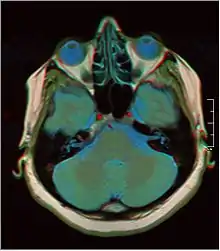

Brain regions on T1 MRI

T1 (note CSF is dark) with contrast (arrow pointing to meningioma of the falx)